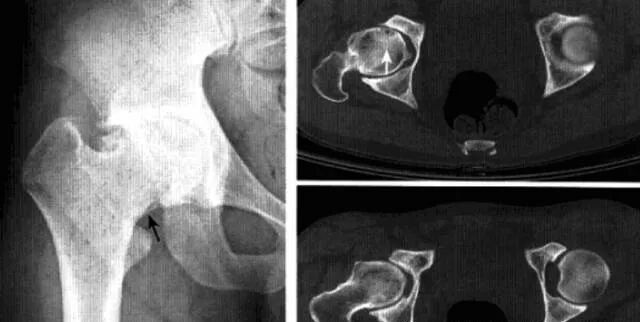

髋关节撞击综合征

也称股骨髋臼撞击综合征,是由于股骨近端和髋臼盂缘间解剖的异常,或解剖正常但长期不正常外力作用于髋关节,导致两者长期不正常接触、碰撞,产生反复的微型创伤致使关节盂缘和关节软骨退变,从而引起慢性髋关节疼痛及髋关节屈曲和内收受限的疾病。分为凸轮撞击和钳夹撞击两个类型。

病理:股骨头软骨呈明显退变现象,关节唇骨化、瘢痕化、体积增大、软骨下撕裂。

临床表现:凸轮撞击多见于喜欢运动的青年男性,钳夹撞击多见于活动较多的女性。典型表现为腹股沟区疼痛,通常在活动或久坐后加剧,呈间歇性,后期呈持续性。病变常呈单侧性,查体时髋关节活动受限,撞击试验阳性。

影像诊断:X线平片是基本检查方法,直立骨盆正位及髋关节侧位片。

平片:①凸轮撞击型,正位片示头颈连接处扁平,呈“左轮枪柄”样畸形,侧位片示股骨头颈凹陷减少,*边缘角变小<16度,②钳夹撞击型,髋臼窝过深,髋臼后倾,呈相交8字征,偏心距缩短<9mm。

CT:三维CT可测量股骨头颈连接处前外侧偏移量减低,股骨头颈联合处前上缘可见骨性突起。

MRI:股骨头颈凹陷减少(α>50°),股骨颈宽度与股骨头半径比率增大,髋臼后倾。盂缘退行性改变,撕裂、囊肿,关节间隙后期出现狭窄,周围肌肉炎症。